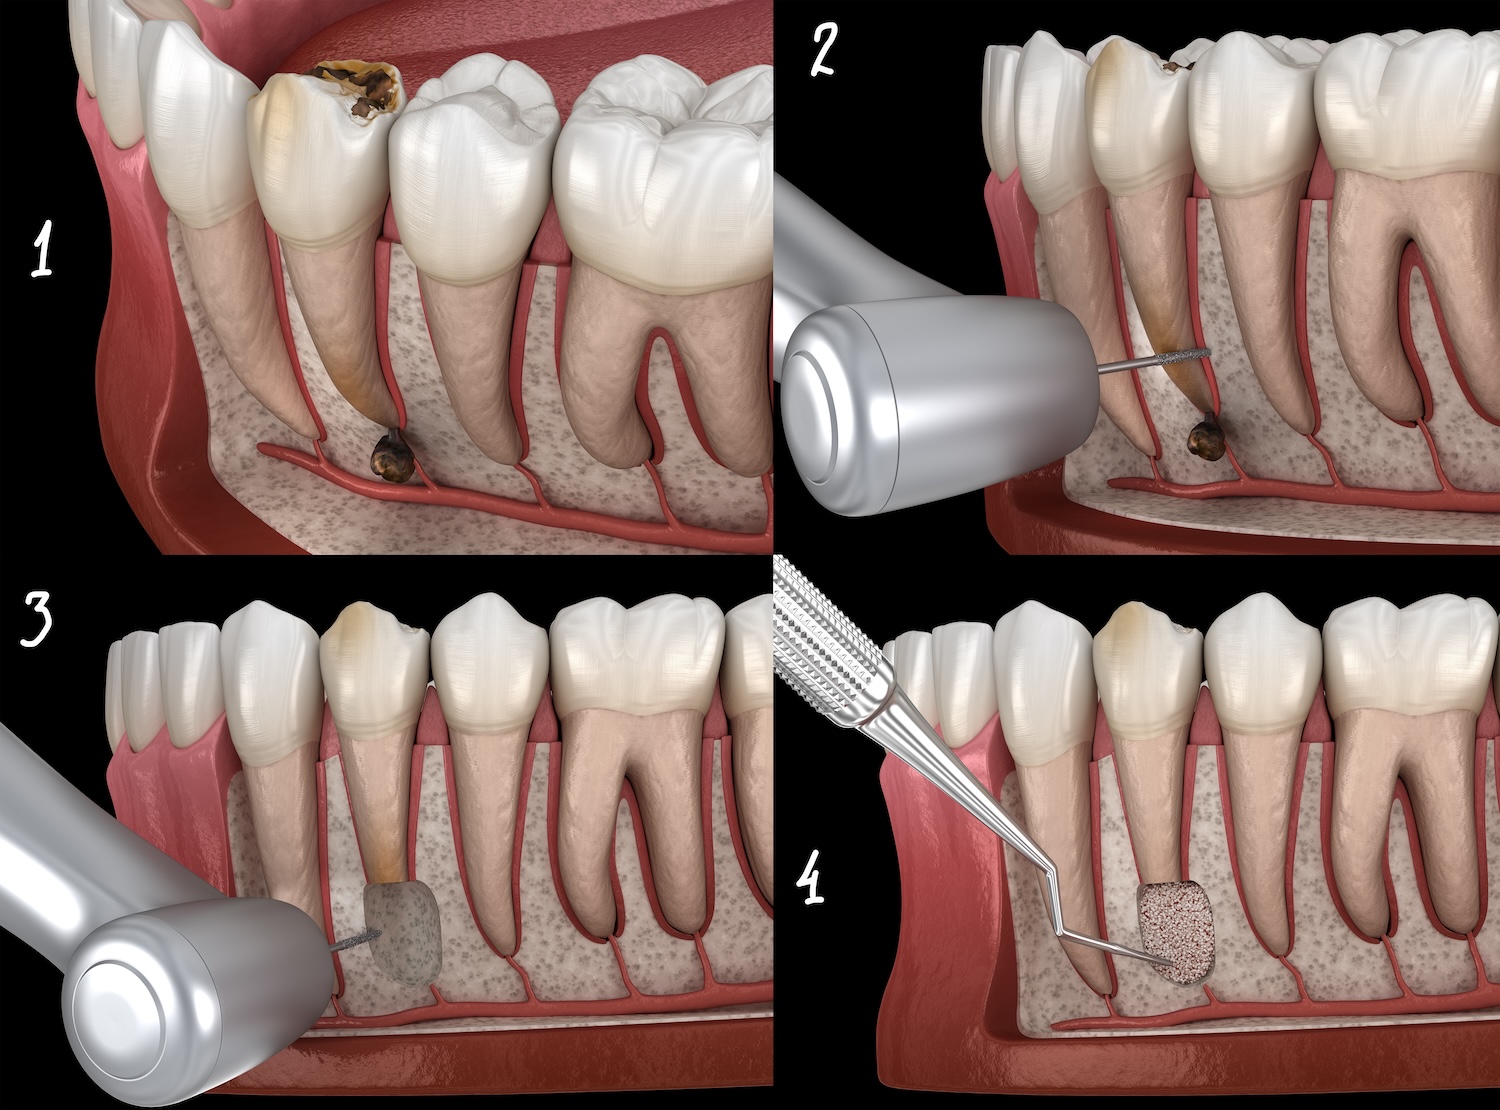

根管治療の流れ

歯根端切除術

歯の根の端を外科的に切断し、周りの膿を掻爬・摘出する方法です。当院ではさらに歯根を切断した後に逆根管窩洞形成・逆根管充塡を行っております。

この治療を行うためには、その他の感染経路の有無、歯根破折の有無を精査する必要があり、歯科用手術顕微鏡での観察が必須になります。

専門的な知識や技術はもちろん、超音波チップやMTAセメントといった先進の医療機器が必須となる治療法といえます。